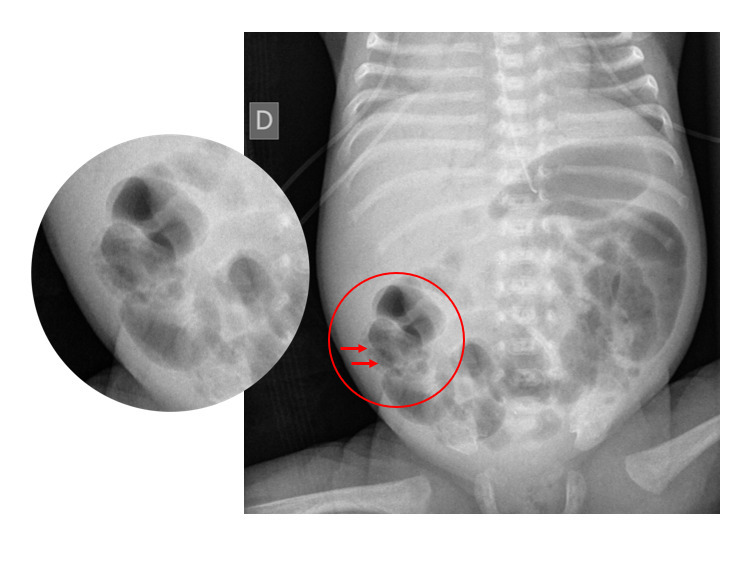

L’ECUN est une pathologie aiguë multifactorielle du tube digestif,1,2 secondaire à une interaction anormale entre le microbiote intestinal et l’épithélium intestinal immature, qui présente un déficit en mucus protecteur et en immunoglobulines A. Il en résulte une réaction inflammatoire excessive associée à une augmentation de la perméabilité de la barrière intestinale et une invasion bactérienne des parois du tube digestif. L’ECUN est caractérisée par une pneumatose intestinale (figure), secondaire à la libération de gaz par les bactéries au sein de la paroi intestinale. Elle peut évoluer vers une perforation digestive et/ou une nécrose intestinale plus ou moins étendue. Cliniquement, l’ECUN se présente comme un syndrome occlusif très douloureux associé à des rectorragies et à des signes de sepsis, avec une altération plus ou moins sévère de l’état général, jusqu’à l’état de choc et la défaillance multiviscérale.